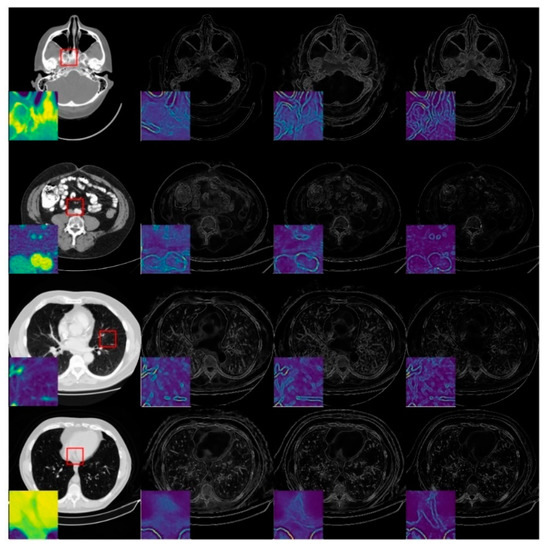

To investigate the degradation perception of the image-domain module, we compared the predicted critical-map of the spatial-attention block for the same image with different degradation levels, as shown in Figure 7. The first column is the ideal CT image, whilst the second, third and fourth columns represent the predicted critical-maps at 60 views, 120 views and 240 views, respectively. We zoomed in on the red square area and displayed it in color to observe the textual details. The edge information of the critical-map increases as the degradation decreases, which indicates that the reconstructed values of the contours are generally inaccurate and the later refining block should enhance the detail recovery and reconstruction. In the case of the large degradation level, the critical-map of the image is blurry, indicating that there are still small artifacts interfering in the flat region, which should be further removed in the refining block to improve the overall intensity recovery.

Figure 7. Examples of predicted critical-maps at 60 views, 120 views and 240 views.